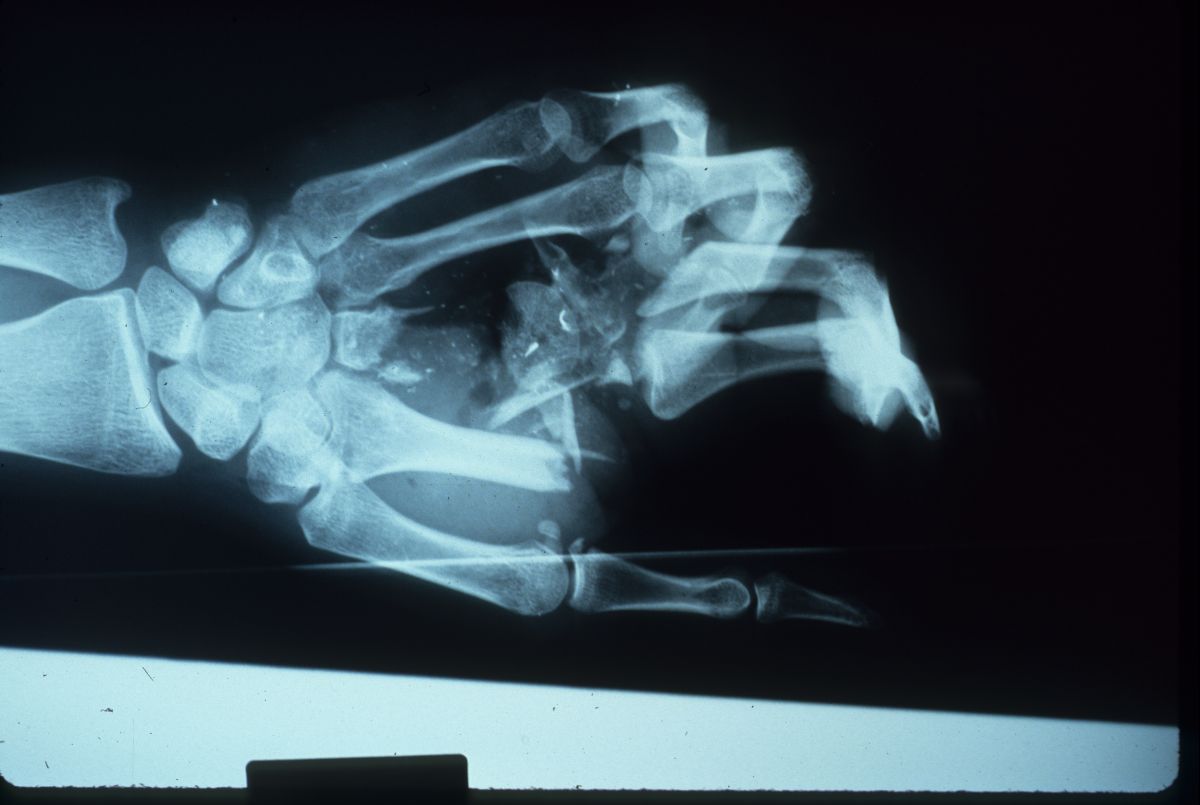

After the flap had healed, the patient was brought back for iliac crest bone graft reconstruction of the index and middle metacarpals. A sterile sponge was used to test a template size of the tricortical graft, which spanned from the proximal carpus to the proximal phalanges. Hunter rods were passed through the graft for extensor tendon grafting at the next stage.

Progression of Xrays: injury; debridement; bone graft; after hardware removal: